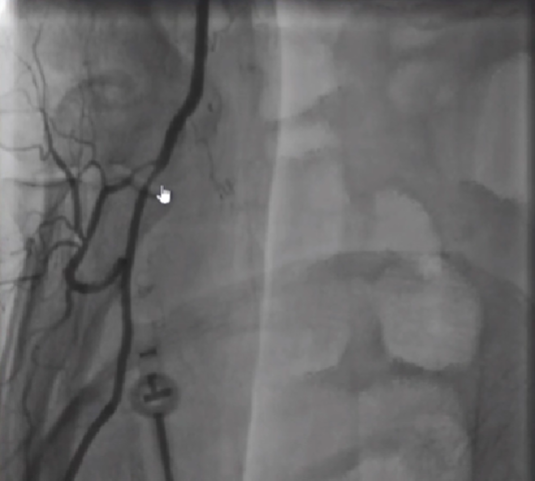

Case 1 桡动脉细小、破裂

图①:桡动脉发生痉挛破裂的地方就在动脉鞘的出口,它的破裂基本都是人为造成的,送入导管的时候过于粗暴。所以导管通过动脉鞘出口的时候一定要慢。

图②:使用BAT技术,球囊一半在导管里面。一半在导管外面,然后一起往里面送,很容易通过痉挛的地方。

图③:做完PCI回过头来看,这根桡动脉已经修复的很好。